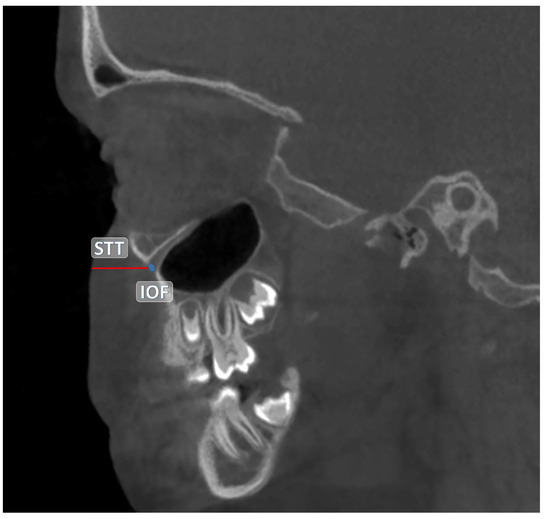

The central point of the infraorbital foramen (IOF) was used as the reference in all measurements. The anatomical landmarks used as references in the study are detailed in Table 1. All measurements were performed in millimeters (mm) based on CBCT images. The distances between the reference anatomical landmarks and the IOF are illustrated in Figure 1 and Figure 2. Additionally, the soft tissue thickness (STT) on the buccal side of the IOF was assessed using sagittal CBCT sections (Figure 3).

Figure 3. Measurement of the soft tissue thickness (STT) buccal to the IOF in sagittal CBCT sections.

The soft tissue thickness over the IOF (IOF-STT) was found to be 11.49 ± 1.74 mm on the CS and 11.47 ± 1.65 mm on the NCS. However, no significant difference was observed between the two groups (p > 0.05) (Table 4).

The estimation of soft tissue thickness over the IOF is clinically important, especially to prevent excessive needle penetration during anesthesia administration, thereby reducing the risk of trauma to the orbit and surrounding anatomical structures [35,41]. In the present study, no significant difference was found in soft tissue thickness over the IOF between the CS and NCS (p > 0.05). This finding is consistent with previous studies conducted on healthy individuals [29,35,41]. The lack of difference in soft tissue thickness suggests that the standard needle depth used in anesthesia procedures can be applied safely in individuals with UCLP as well.